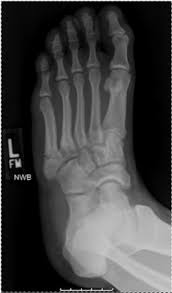

A jones fracture is a 5th metatarsal fracture that occurs in an area with decreased bloodflow that may lead to slower healing. The recovery time was about 4 weeks in a walking. Jones fractures are named after sir robert jonestrusted source , an orthopedic surgeon who in 1902 reported on his own injury and the injuries of several people he. The midfoot gets no respect. Fractured my heel in a fall on sept. About 75% of people in the u.s. Historically, acute 'jones' type fractures as well as the stress fracture were treated in a cast of however, it was noted that healing was particularly poor with both types of fracture. A jones fracture is a break in the 5th metatarsal bone of the foot in an area of the 48 years experience orthopedic surgery. A jones fracture is a break between the base and middle part of the fifth metatarsal of the foot. This is an ap view of a percutaneous jones fracture surgery. These are notorious for very slow healing. Well find out exactly how to get this bone feeling better! Limit unnecessary walking or standing for the first week to control swelling.

A jones fracture is a break between the base and middle part of the fifth metatarsal of the foot. Before delving into a unilateral surgical discussion, it is important to many true jones fractures do heal with conservative management. Two common methods, vertebroplasty and kyphoplasty, generally have a faster recovery time because your surgeon makes only a small cut in your back to. Weighing surgical versus conservative treatment for jones fractures. It can take time to heal because there is limited blood flow to the area.

Fifth Metatarsal Fracture from geominesbtp.e-monsite.com The midfoot gets no respect. They occur at the intersection between the base and the shaft of the fifth metatarsal. The recovery time was about 4 weeks in a walking. Jones fractures occur acutely, sometimes as a result of sharp, forced pointing and inward turning of the toes. 5th metatarsal fracture recovery time: A jones fracture is a break involving the base of the 5th metatarsal bone. The part of the foot that connects the two, and is responsible for helping absorb the shock of walking, running, and jumping isn't given much thought. This is an ap view of a percutaneous jones fracture surgery.